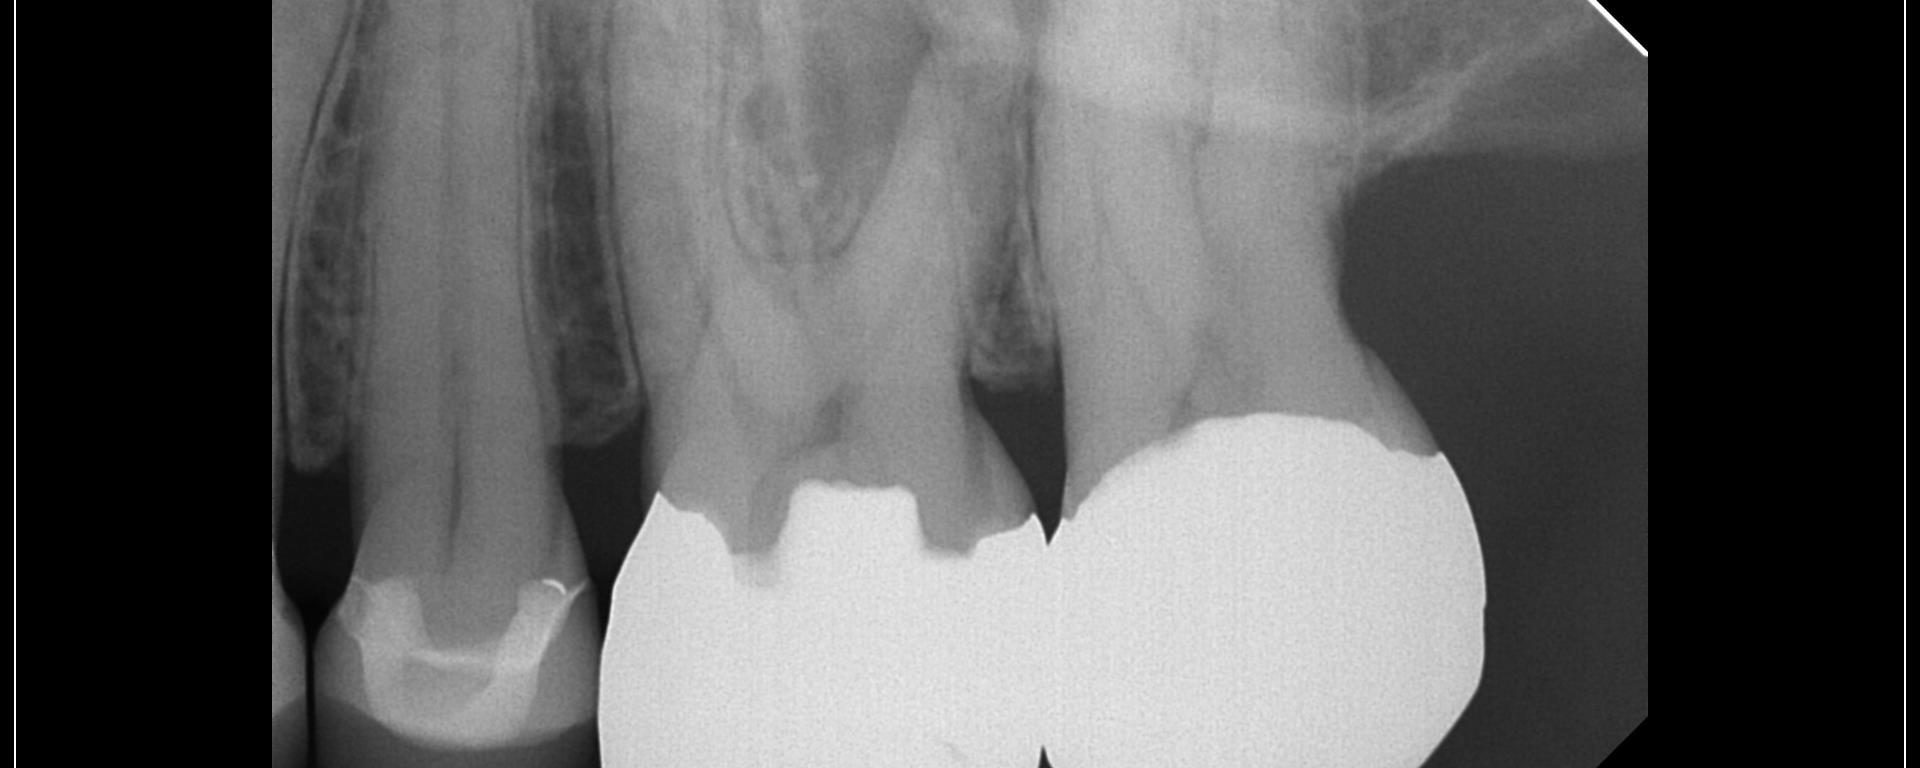

Scheduled for a GW…then I took a CBCT…….. No way, Jose……. Tried to minimize the access just for practice…… not even close to Nishan territory but still trying….. gbc